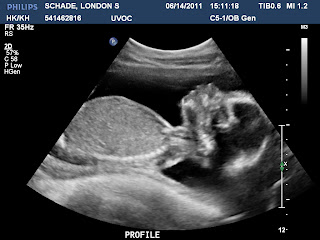

Today we went to the Provo hospital and had some pictures taken. I have to say you gave the ultrasound student quite the runaround. Just as she was about the freeze the frame for a shot they needed you would twist and turn and tuck and roll. Both nurses knew you were a boy before we even got the money shot. They said, “Boys are the only ones moving this much.” I agreed when the ultrasound tech called you a little turd, but must confess I can’t wait to see what that equates to once you are here in person. I cant say I am excited for tantrums and fits, but I am excited for all those wiggling and stretching fingers and toes.

You are famous by the way. Your Papa and I watched you on the T.V. for about 45 minutes and loved every minute of it. Best, most exciting feature I have seen on T.V. ever! We even got to see the lenses of your eyes, the shape of your nose, your little mouth. Most of the images were used for measurements. We saw your stomach, C spine, heart and a bunch of other blobs I had no idea what they were. The ultrasound techs couldn’t really tell us much about the things they were looking at, whether they were normal or not. The only thing we really got was that you are either growing very fast, or we have the due date wrong. Either way you are at about 22 weeks from what they say. That makes me kind of excited because maybe your birthday will be on Halloween! How cool would that be, baby?